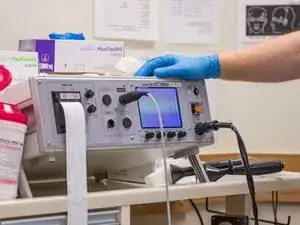

Clinical equipment refers to medical devices that are widely used in clinical settings for patient care. This includes devices like patient monitors, dialysis machines, ventilators, thermometers, stethoscopes, nebulizers, blood pressure monitors, etc.